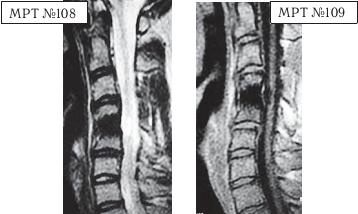

На МРТ № 108 состояние шейного отдела позвоночника пациента через 11 месяцев после дискэктомии с межтеловым спондилодезом в сегменте СIV—СV Наблюдается постхирургическая травма спинного мозга на данном уровне хирургической фрезой, кифозирование физиологического лордоза, стеноз позвоночного канала с блоком ликворных путей. На МРТ № 109 состояние шейного отдела позвоночника того же пациента через 23 месяца после дискэктомии с межтеловым спондилодезом в сегменте CIV-CV Наблюдается усугубление стеноза (абсолютный стеноз), спондилолистез (смещение вышележащего позвонка по отношению к нижележащему) СII— СIII, секвестрированная грыжа межпозвонкового диска CV—CVI. На данных снимках наглядно отображается, как подобные операции усугубляют биомеханические нарушения и тем самым способствуют развитию дегенеративно-дистрофического процесса в других сегментах позвоночника. Во время операции грыжу межпозвонкового диска в данном сегменте убрали. Но причины, которые как раз и спровоцировали образование грыжи, а именно биомеханические нарушения (дегенерация выше- и нижележащих межпозвонковых дисков, стеноз, кифоз), как были, так и остались! Несмотря на то что отдалённые последствия этой операции легко прогнозировались и полученный результат, как факт, абсолютно закономерен, подобные операции, к сожалению, как делались, так и делаются и, пожалуй, самое печальное, что и будут делаться дальше. Случаи послеоперационных рецидивов грыж межпозвонкового диска бывают разные, но причины, как правило, идентичны. Вот одна из типичных ситуаций. Врачи во главе с хирургом после хирургической операции пациента по поводу грыжи межпозвонкового диска в сегменте LV-SI в качестве профилактики посоветовали ему заниматься вытяжением позвоночника под собственным весом и укреплением мышечного корсета путём выполнения специальных упражнений на наклонной плоскости. Результат усердия пациента, последовавшего такому совету, можно наблюдать на МРТ № 110 (см. стр. 286). Исходя из анатомического и физиологического строения позвоночника человека и неизбежного действия законов физики, результат от такой «профилактики» вполне прогнозируем. Поэтому логично предположить, что врачи, посоветовавшие данному пациенту такую «профилактику», спровоцировавшую секвестрированную грыжу межпозвонкового диска в сегменте L^ — Ly, просто не знали о её последствиях. Если бы здоровье пациента позволило бы продолжить эти упражнения, то аналогичные осложнения неизбежно образовались бы и в вышележащих позвоночнодвигательных сегментах. ![]() На МРТ № 110 наблюдается состояние поясничного отдела позвоночника: секвестрированная грыжа межпозвонкового диска в сегменте LIV-LV с разрывом задней продольной связки, абсолютный стеноз спинномозгового канала. Но не спешите обвинять хирургов. Как бы это странно не звучало, это не их вина — они всего лишь удаляют часть ткани организма (грыжу). Ведь профессия хирурга заключается в знании и умении оказать пациенту своевременную хирургическую помощь, а вот послеоперационным восстановлением и «профилактикой» должны заниматься врачи-реабилитологи. Даже самые лучшие хирурги в мире, в совершенстве владеющие своей специальностью, за пределами операционной становятся обыкновенными людьми, которым, как и многим, свойственен относительный процесс познания. Требовать от них большего, это значит требовать от человека абсолютного процесса познания. Если вы считаете, что на это способен любой человек, попробуйте начать с себя. Гораздо хуже, когда врачи-реабилитологи в качестве «профилактики» дают такие «советы», вот это уже можно назвать профессиональной безграмотностью. Вот ещё случаи послеоперационных рецидивов грыж — естественной реакции организма, когда проблема решается однобоко — всего лишь с помощью хирургической операции в поражённом сегменте без общего восстановления биомеханики позвоночника.